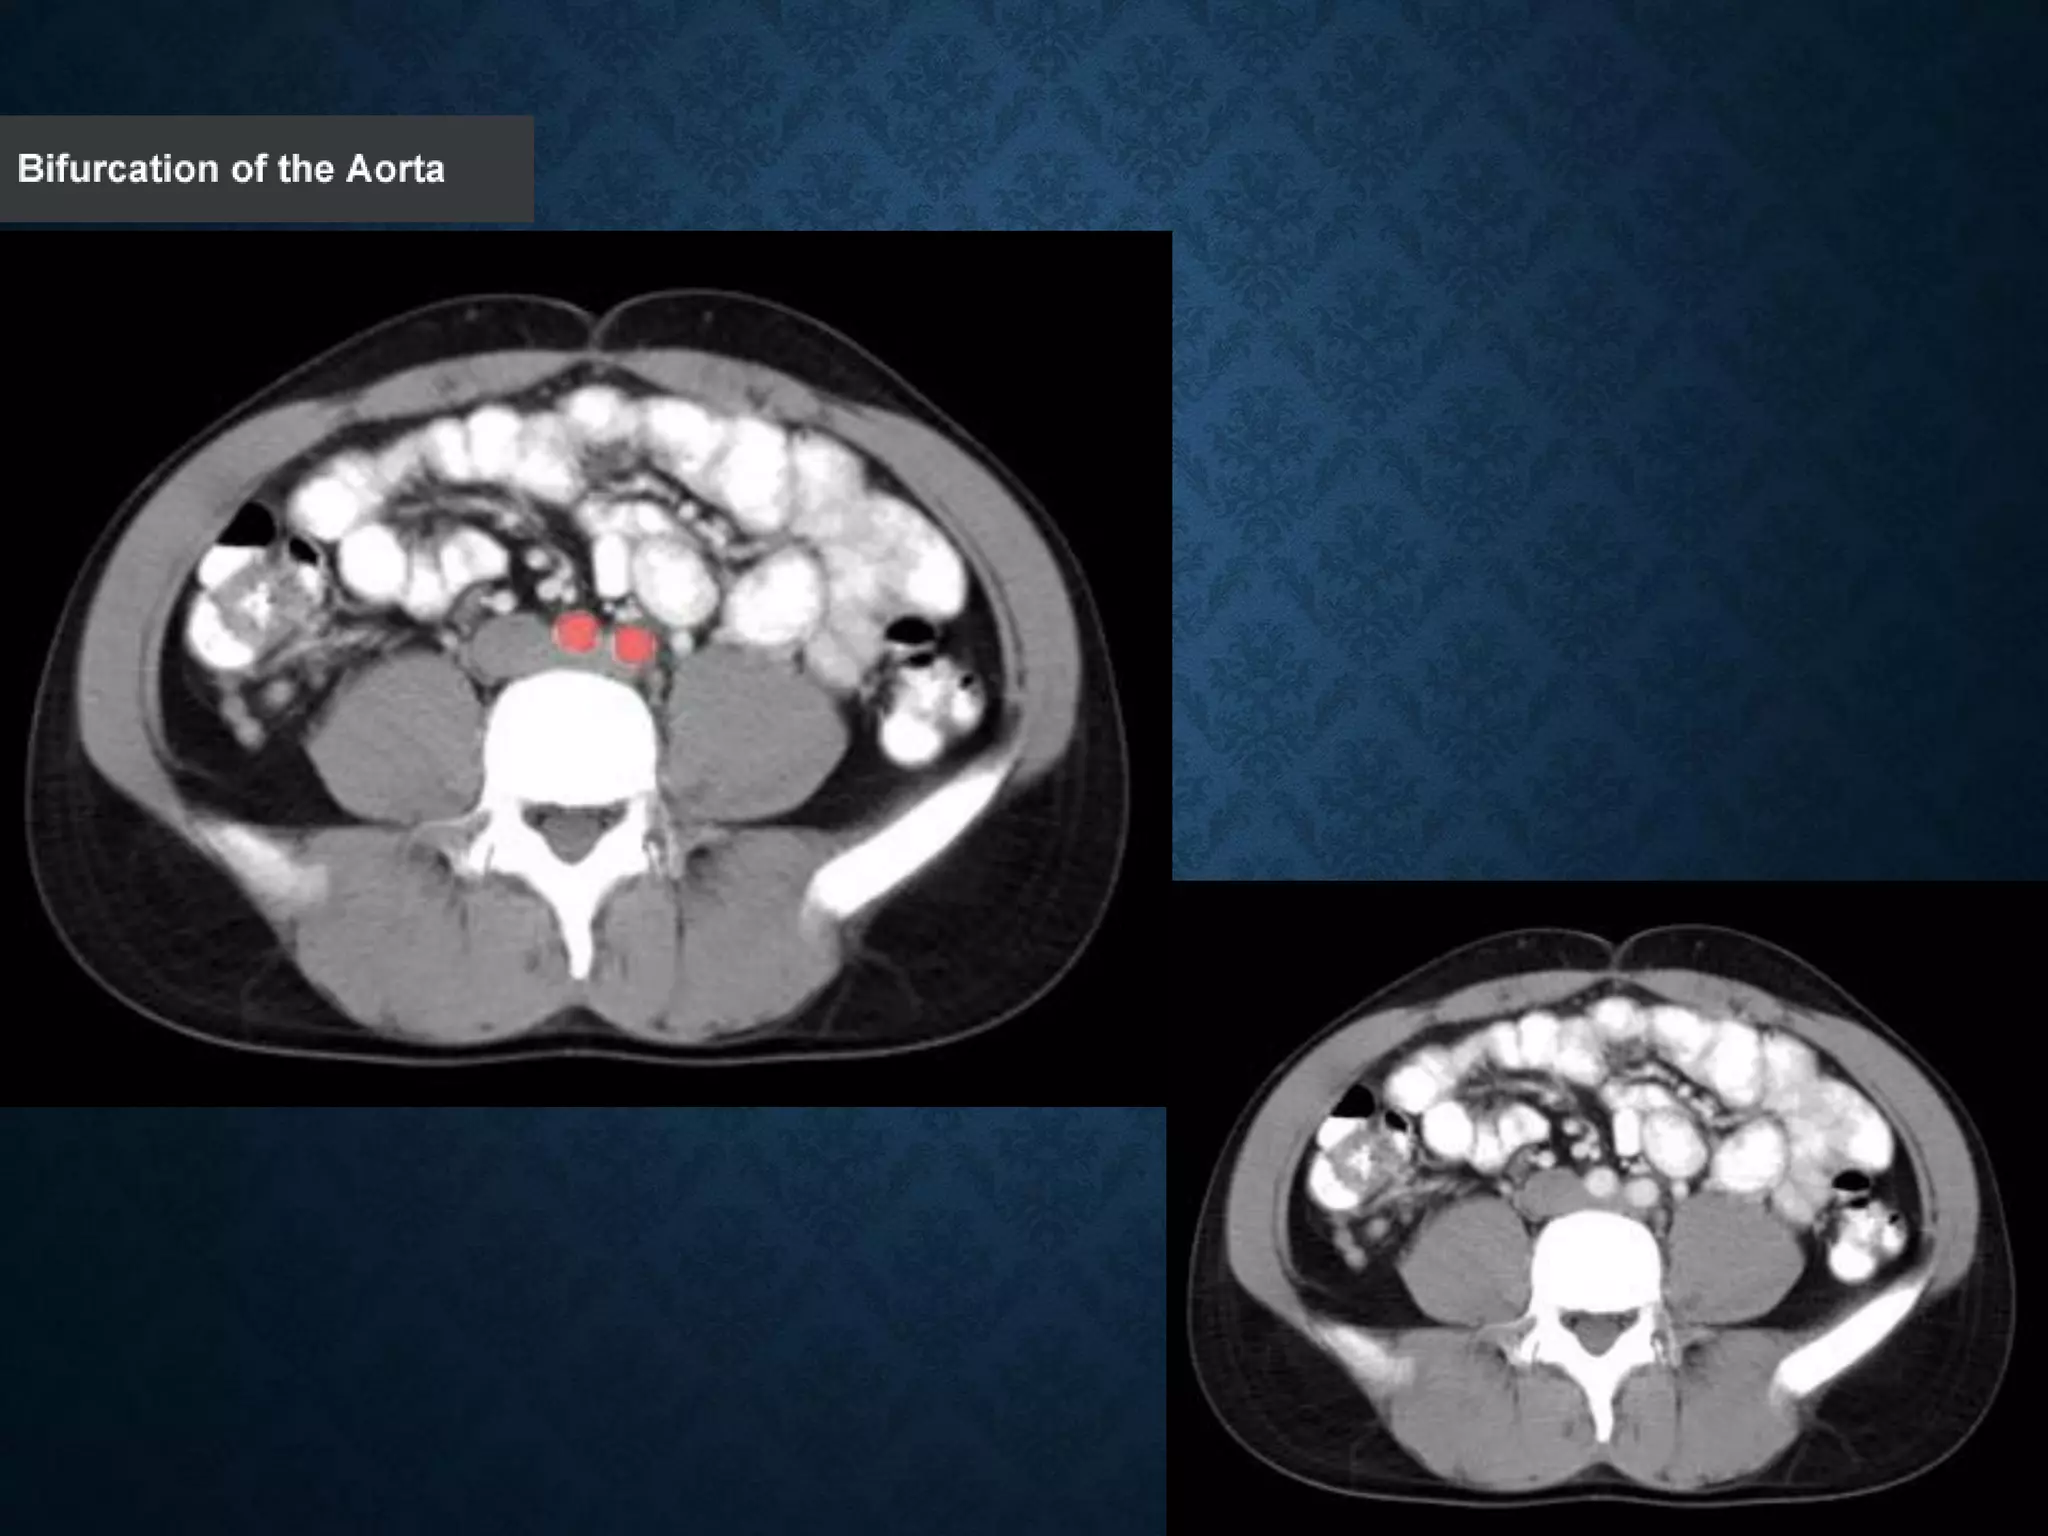

ABDOMINAL AORTA

origin: Continuation of descending thoracic aorta at T12

• course: descends anterior and slightly to the left of the lumbar vertebral

bodies.

•Bifurcation of aorta:L4

• Note that the bifurcation (union) of the inferior vena cava is at L5and

therefore below that of the bifurcation of the aorta)

ABDOMINAL AORTA origin: Continuationof descending thoracic aorta at T12 • course: descends anterior and slightly to the left of the lumbar vertebral bodies. •Bifurcation of aorta:L4 • Note that the bifurcation (union) of the inferior vena cava is at L5and therefore below that of the bifurcation of the aorta)